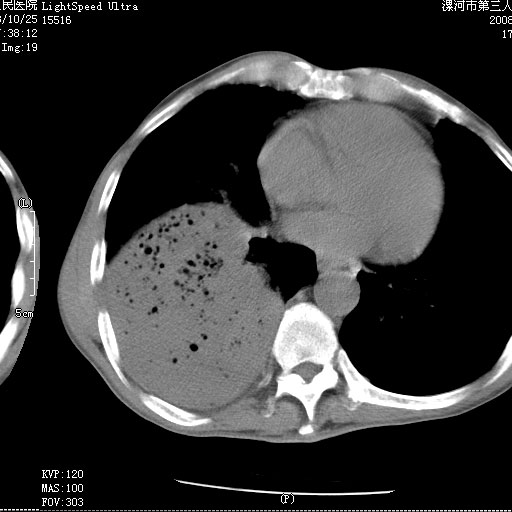

m 老年 发烧、呼吸困难,慢支、肺气肿多年;记的那次是下午大概17:38做的,晚上窒息死亡。

上面的层面就慢性支气管炎肺气肿、肺大泡,别的没有什么、也就不传了。

当时我怀疑:1、阻塞性肺不张早期 2、肺脓肿早期,望老师们发表意见

应该是脓胸的表现,右下肺气管阻塞考虑为痰栓.

你怀疑的有道理,慢支、肺气肿、肺打泡是有了,右下肺的病变有待商议;

首先考虑右下肺炎症并不张,不除外早期肺泡癌改变

病灶边缘清---多个含气小腔---近端未见通畅气管影-----支持-----慢性肺脓肿继发阻塞性肺不张

阻塞性肺不张原因-----脓液未排出

3、细支气管肺泡癌可以排除,病变以斜裂为界,呈大片状高密度影,内可见多发小气泡,表明有产气杆菌感染所致,内无明显的支气管“枯树枝征”表现,再结合其临床改变(细支气管肺泡癌临表表现重、影像表现轻)所以不符合细支气管肺泡癌(炎症型)的改变。

病变按肺叶分布,病变内可见多个小空腔影,未见充气支气管影,中间段支气管管腔肺窗示密度欠均匀,下肺支气管分叉处基底段支气管隐约可见,未见明显狭窄,中叶支气管通畅,

考虑:阻塞性肺炎伴小脓肿形成可能性大。(痰栓可能性大)

右下肺实变,内有弥漫分面小气泡而无支气管征,叶间裂前移,呈臌大之形,而无收缩之状,兼纵隔稍左行移,故。不支持不张,倒支持大叶肺叶,如楼上所说,小气泡不象残留之肺,不可以考虑产气菌感染吗。

阻塞性肺炎,肺脓肿形成。依据,右下支气管不通,大片实变形内可见小气泡。不支持肺不张。